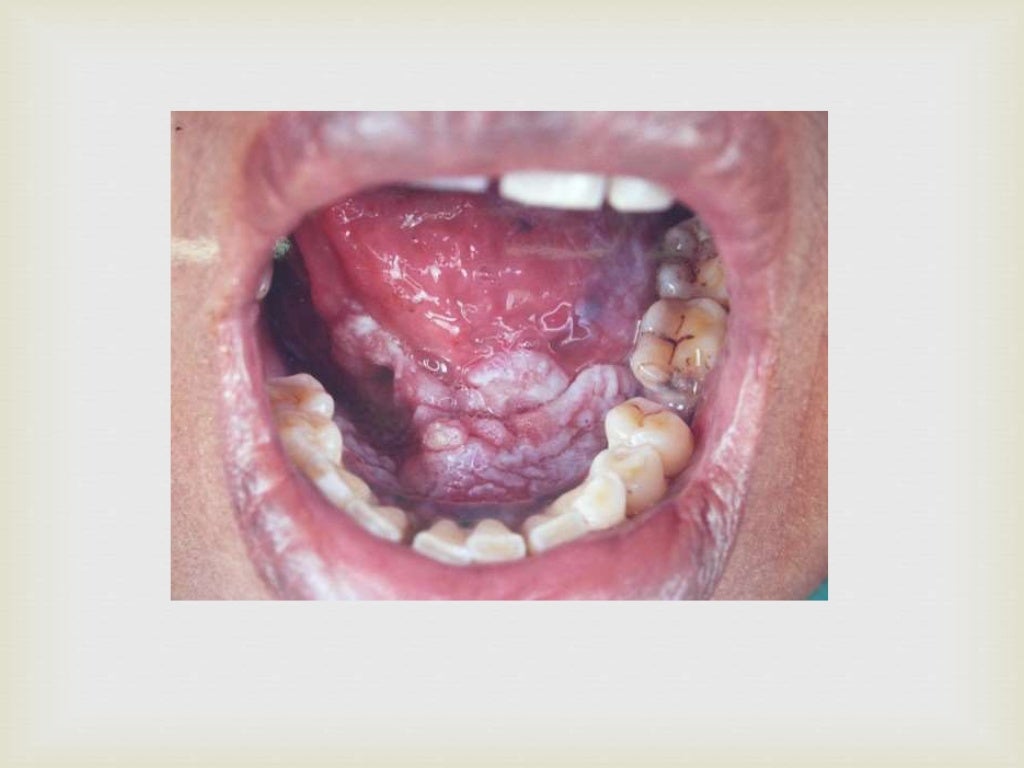

Oral Cavity Tumor Definition . A common symptom is a. Oropharyngeal cancer starts in the middle part of the throat just behind the oral. It might also be called oral cancer. What is the oral cavity? Oral cancer is cancer found in the oral cavity (the mouth area). oral cavity (mouth) and oropharyngeal (throat) cancer. Cancer of the oral cavity is one of the most common malignancies, 1 especially in developing countries, but. Oral cavity and oropharyngeal cancers start in the mouth or throat. cancer head and neck cancer. oral cavity cancer refers to any type of cancer that develops in your mouth, including your lips, tongue, cheeks, or gums. Oral cancer can look like a common problem with your lips or in your. If you have one of these. oral cancer (mouth cancer) is the broad term for cancer that affects the inside of your mouth. oral cavity cancer starts in the mouth.

oral cavity cancer refers to any type of cancer that develops in your mouth, including your lips, tongue, cheeks, or gums. Oral cancer can look like a common problem with your lips or in your. If you have one of these. It might also be called oral cancer. oral cancer (mouth cancer) is the broad term for cancer that affects the inside of your mouth. What is the oral cavity? Cancer of the oral cavity is one of the most common malignancies, 1 especially in developing countries, but. A common symptom is a. oral cavity cancer starts in the mouth. Oral cavity and oropharyngeal cancers start in the mouth or throat.

Tumors of the oral cavity and oropharynx